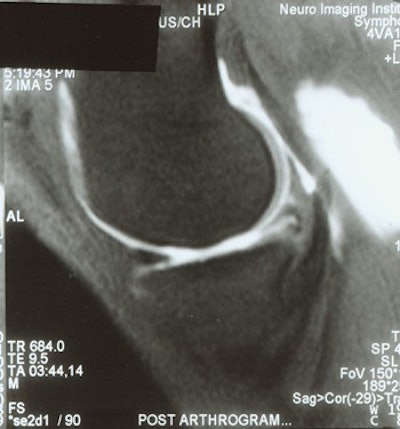

![]() |

| MR arthrogram demonstrates no meniscal tear in a patient with >25% meniscal resection. Images courtesy of Dr. Thomas Magee. |